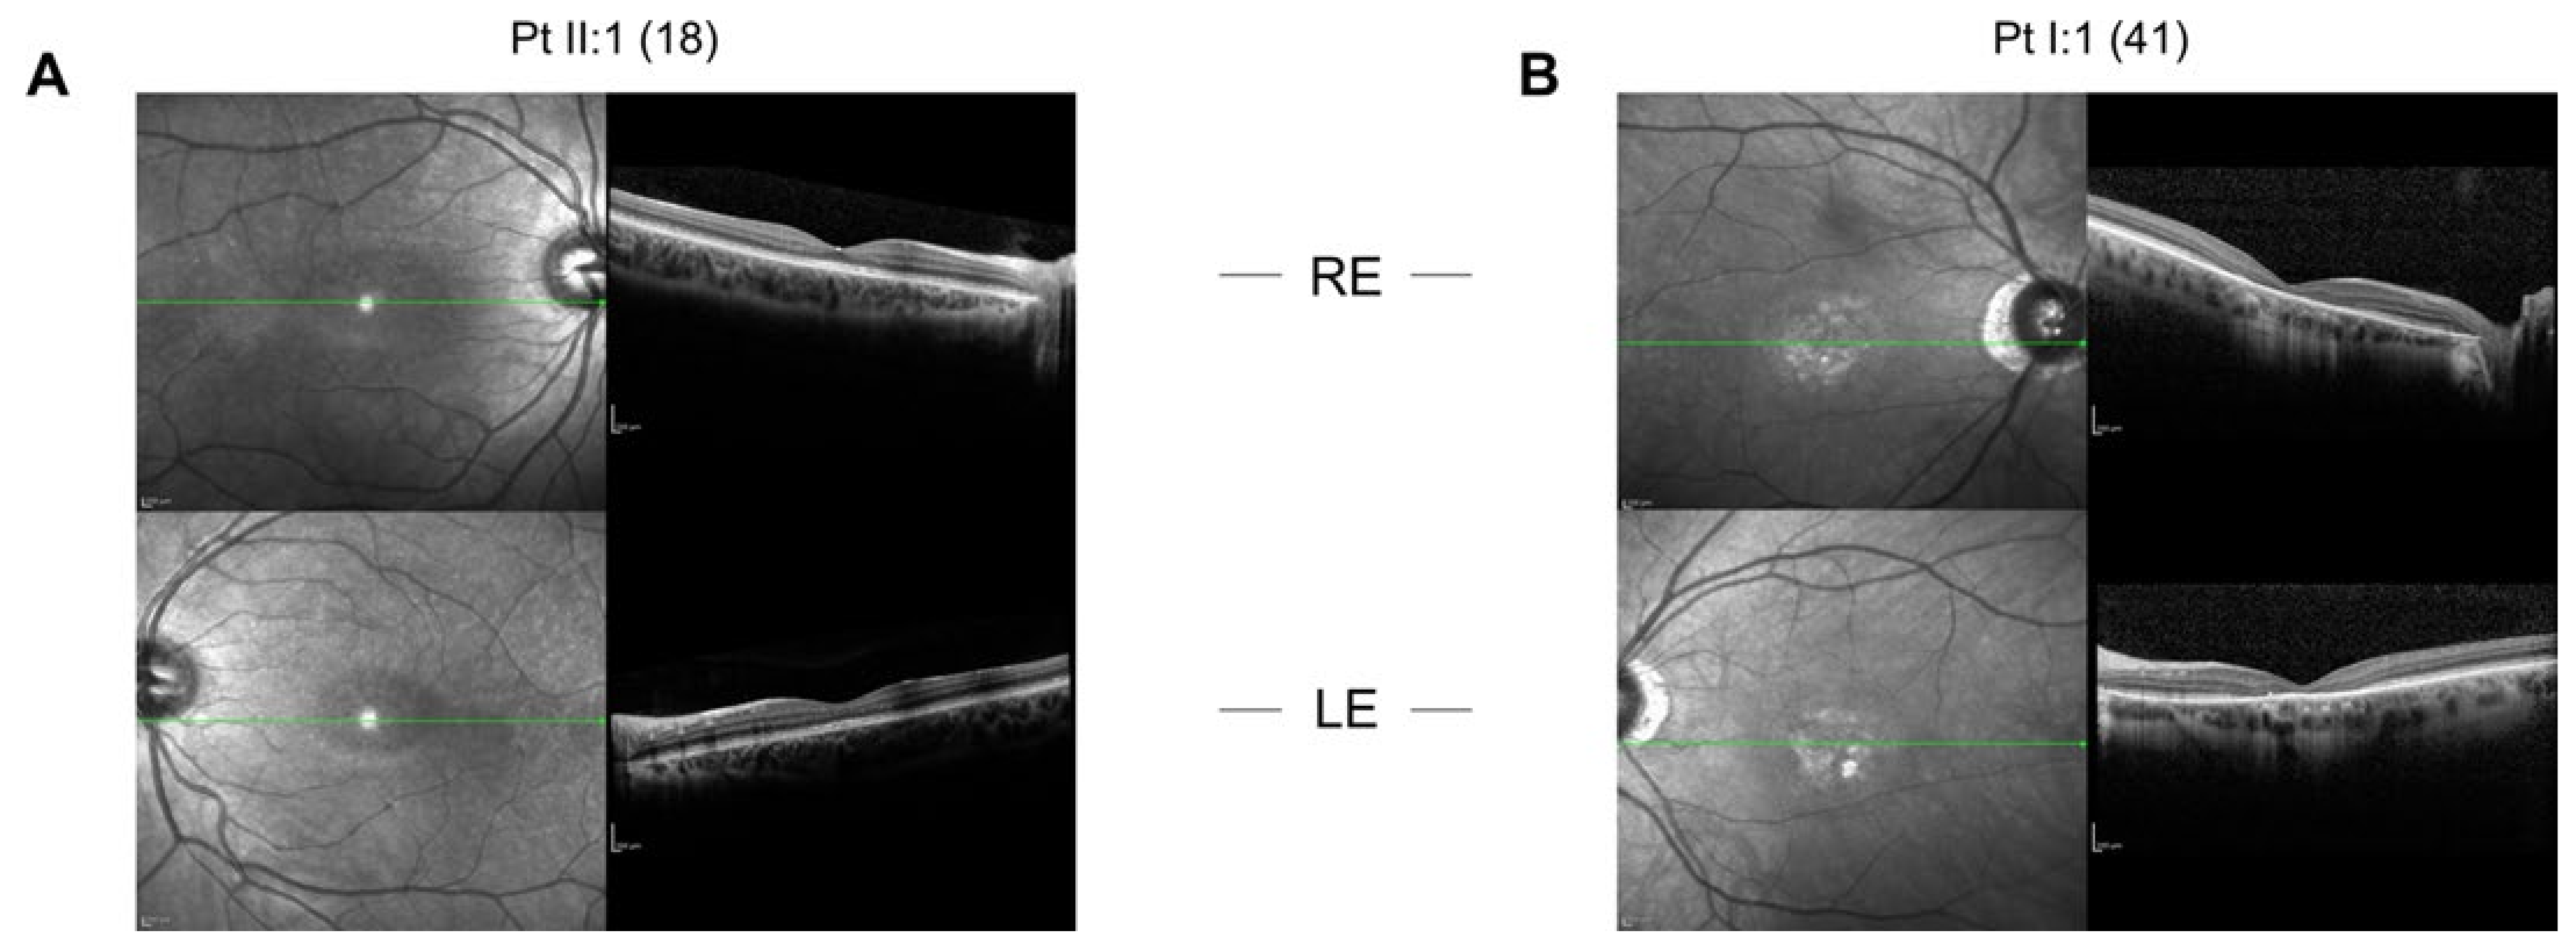

2.1.1. Patient 1

2.1.2. Patient 2